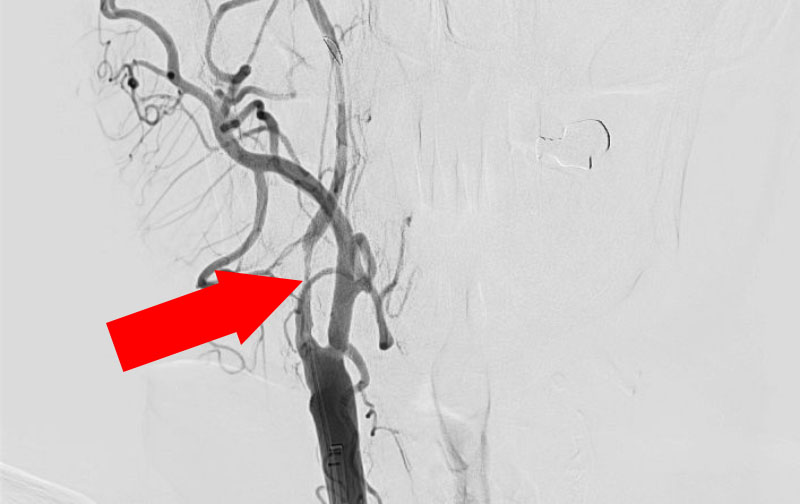

No.1243 手術中